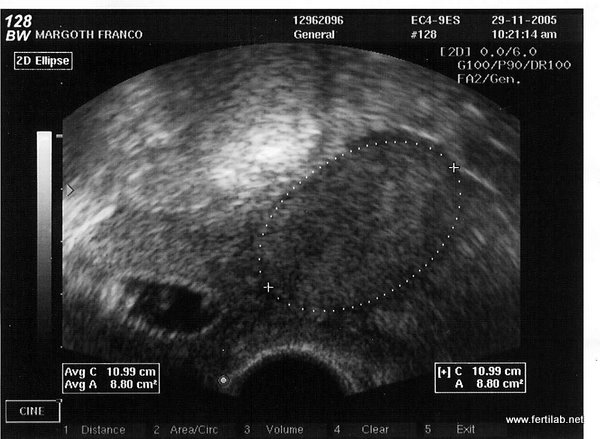

Mioma con embarazo | |

El impacto que tiene la miomatosis uterina sobre el éxito de estos procedimientos es controversial. Existen múltiples estudios que señalan que la presencia de miomas submucosos disminuye la tasa de embarazo a menos de la mitad y, por tanto, siempre deben ser removidos.

El dilema se presenta cuando los tumores son “intramurales” que no protruyen hacia la cavidad o los “subserosos” de gran volumen, porque algunos estudios señalan que si los tumores son de menos de 4 cm se puede realizar el procedimiento de fertilización in vitro sin practicar una miomectomía previa.